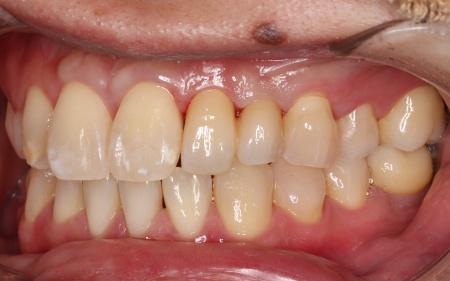

30代男性 歯が欠損した部分を片側固定ブリッジで補った症例

「大人になってからも残っていた乳歯が抜けてしまったので、歯を入れたい」とご相談いただきました。

拝見したところ、左上の糸切り歯が欠損していました。

これまでは乳歯が残っていたものの、最近になって自然に抜けてしまったとのことです。

レントゲン検査で詳しく調べた結果、患者様は生まれつき左上の糸切り歯の永久歯が存在しないことが分かりました。

このケースでは、乳歯が抜けてしまうと今後歯が生えてくることはありません。

欠損したままの状態を放置すると、前後の歯が徐々に動いて歯並びが乱れたり噛み合わせに影響が出たりする可能性があります。